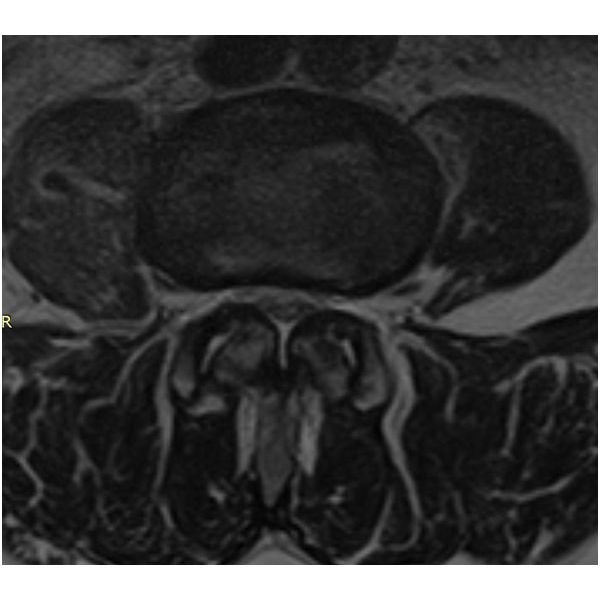

МРТ поясничного отдела позвоночника подтвердило диагноз.

Остеохондроз поясничного отдела позвоночника, дегенеративный спондилолистез (смещение) L3, спондилоартроз 3–4-й (тяжёлой) степени, функциональная несостоятельность позвоночника, нестабильность сегмента и дегенеративный стеноз позвоночного канала на уровне L3–L4 (по классификации Schizas — степень С), нейрогенная перемежающаяся хромота, люмбалгия.